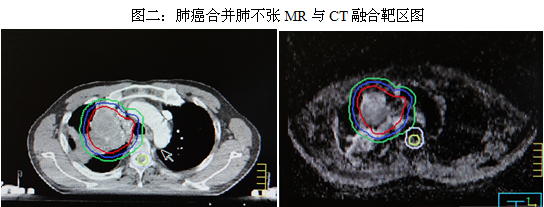

二、MR与CT图像融合定位技术在肺癌合并肺不张放疗中的应用

以往肺癌合并肺不张患者放疗前是应用CT模拟定位,在CT图像上医生不能准确判断肿瘤与不张的正常组织界限,这就使得靶区(肿瘤区)勾画不精准,正常肺组织受到较高剂量照射。目前最好的定位方式是PET-CT,它可以准确分辨肿瘤与不张的界限。我科已开展这一定位技术。MR对软组织有较高分辨率,依据肿瘤与不张的肺组织在MR上的信号特点不同可以区分二者,准确找出肿瘤区。在判定肿瘤与不张的正常组织方面MR较CT有优势。所以放疗前依据MR图像勾画靶区(肿瘤区),然后在TPS上与定位CT图像融合,制定治疗计划。我科与放射科协作开展了肺癌合并肺不张的三维适形及调强放疗MR与CT图像融合定位技术,应用效果较好。